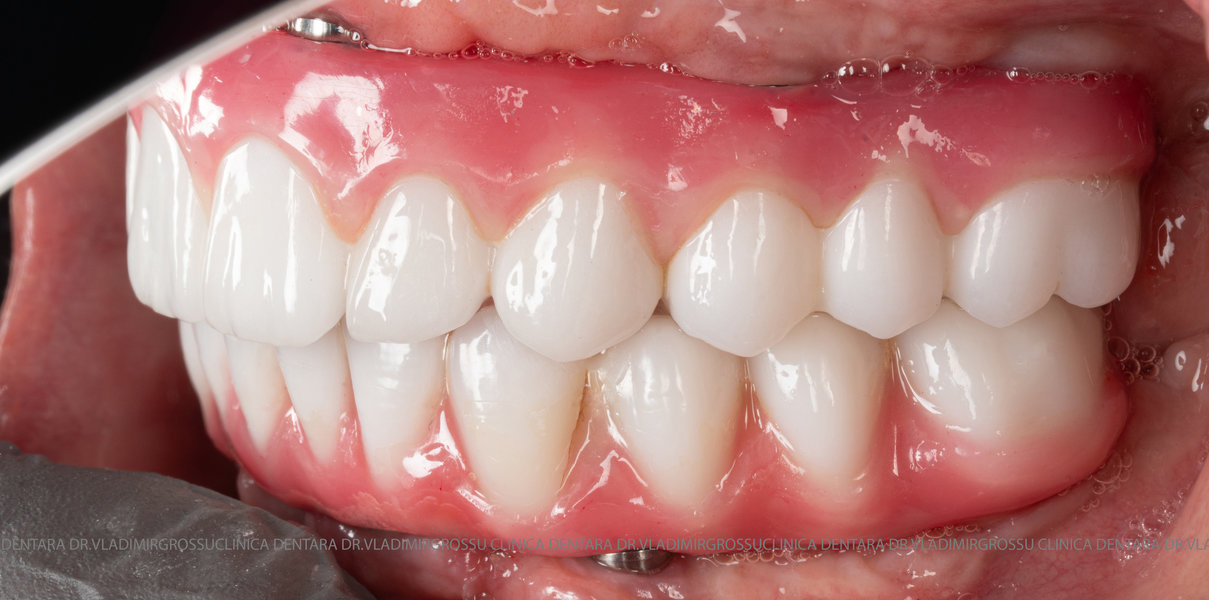

- A doua etapă are loc la aproximativ 6 luni după intervenție, când se realizează proteza definitivă, care este fixată pe implanturi prin intermediul unor piese numite multiunit-uri. Această etapă presupune lucrul la nivelul multiunit-urilor, nu direct pe implanturi, reducând astfel riscul de complicații.

Caz 2

- Posibilitatea realizării unei proteze cu 12-14 dinți, oferind un aspect estetic natural și funcționalitate optimă.